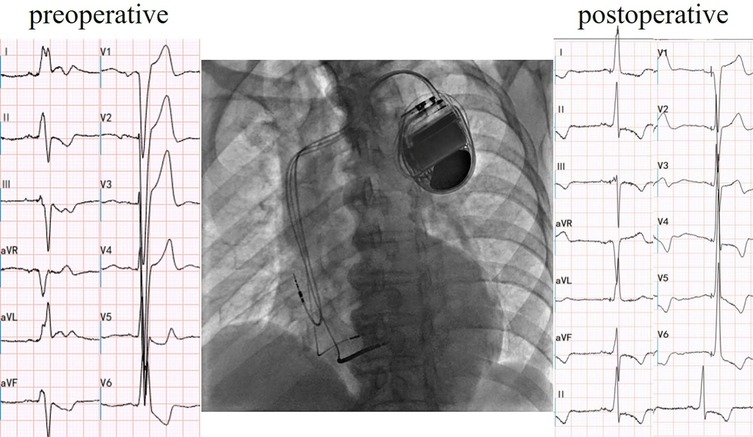

Figure 2

Cardiac resynchronization therapy-defibrillator with left bundle branch area pacing. Electric axis and QRS duration of postoperative were −6° and 106 ms, respectively.

Cardiac resynchronization therapy-defibrillator (CRT-D) with LBBAP was successfully implemented for the patient, achieving LBBAP with a QRS duration of 106 ms during the procedure(Figure 2). At the time of implantation, threshold testing revealed a transition from a wider, fused QRS to a narrower fully-paced QRS. The paced QRS showed a V6 RWPT of 93 ms and a V6–V1 interpeak interval of 10 ms. These findings are consistent with LBBAP. Notably, left axis deviation was not observed. The patient was subsequently prescribed oral medications for long-term management, including Rivaroxaban (15 mg, once nightly), Bisoprolol fumarate (2.5 mg, once daily), Atorvastatin (20 mg, once nightly), and Sacubitril/Valsartan (25 mg, twice daily).

The preoperative electrocardiogram indicated a left-axis deviation, while the postoperative electrocardiogram immediately showed a restoration to a normal axis. There are two possible reasons for the change in axis: 1. Alteration in the sequence of ventricular excitation in the conduction system, such as in this case where the left anterior branch conduction speed increased, correcting the relative left anterior branch block; 2. Gradual restoration of cardiac structure, which takes some time. Intraventricular longitudinal mechanical delay was significantly reduced, with the longest delay consistently observed at the anterior wall. This suggests that LBBAP did not modify the sequence of depolarization of the left bundle branch; instead, it might have accelerated the conduction of the left bundle branch, especially the left anterior fascicle, facilitated by the pacing electrode providing a higher conduction velocity.